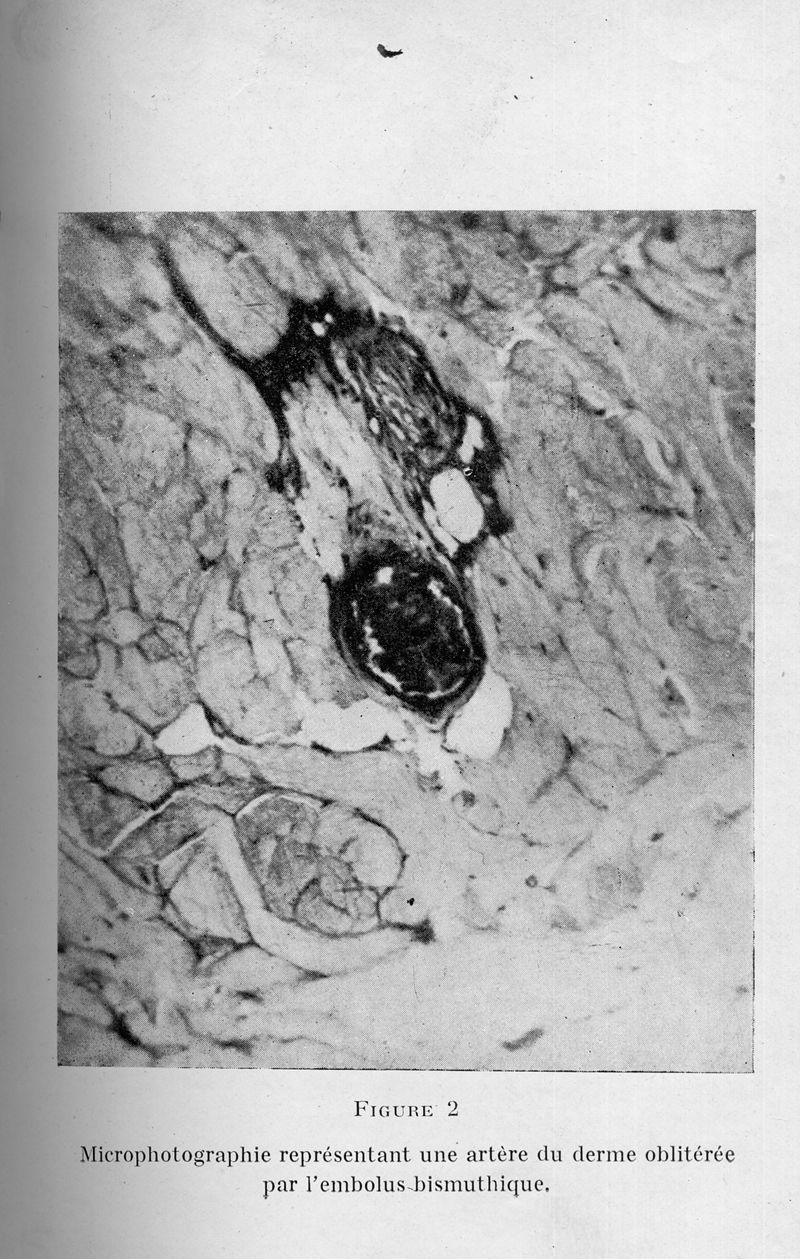

Dermite livédoïde et gangréneuse de la fesse, consécutive aux injections intra-musculaires, dans la syphilis. A propos d'un cas d'embolie artérielle bismuthique

In : Annales des maladies vénériennes, 1925, Vol. 20, pp. 321-39